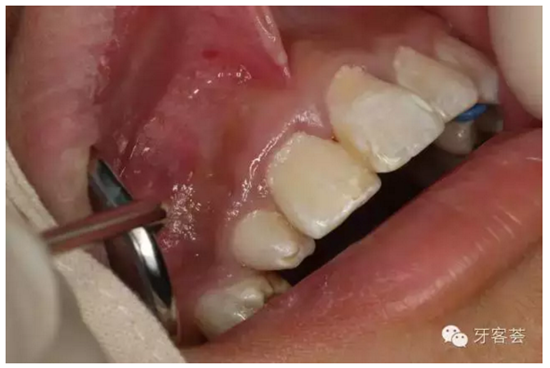

圖5:患者的口內(nèi)像:12位畸形牙,11牙冠顏色無(wú)異常、無(wú)松動(dòng)。